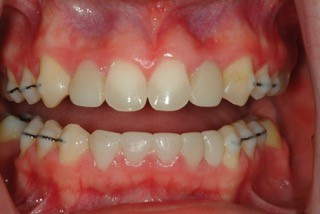

Five years later, Jessica returned to our office to pursue implant treatment. We reviewed her situation and planned for implant placement in the upper and lower posterior segments.

Jessica’s parents wished to stage the implant process and elected to begin in the posterior. The oral surgeon placed the implants, and once healed, screw-retained implant restorations were inserted. The post-treatment images show the molar implants in place. Additionally, seen in the photos are the upper and lower anterior provisional bridges. They remain intact from the original placement date.

Jessica has had no issues or problems with these provisional restorations. Other than some subtle changes in shade, they are expected to remain in place until Jessica is ready to pursue further implant treatment. It has already been more than two years since she had her molar implants restored, and it has been almost eight years since the provisional resin bridges were initially placed.